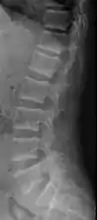

Renal osteodystrophy is usually diagnosed after treatment for end-stage kidney disease begins; however the CKD-MBD starts early in the course of CKD.[1][6] In advanced stages, blood tests will indicate decreased calcium and calcitriol (vitamin D) and increased phosphate, and parathyroid hormone levels. In earlier stages, serum calcium, phosphate levels are normal at the expense of high parathyroid hormone and fibroblast growth factor-23 levels. X-rays will also show bone features of renal osteodystrophy (subperiostic bone resorption, chondrocalcinosis at the knees and pubic symphysis, osteopenia and bone fractures) but may be difficult to differentiate from other conditions. Since the diagnosis of these bone abnormalities cannot be obtained correctly by current clinical, biochemical, and imaging methods (including measurement of bone-mineral density), bone biopsy has been, and still remains, the gold standard analysis for assessing the exact type of renal osteodystrophy.[6][16]

18. 1 2 3 4 5 6 7 Patel, Anish A.; Ramanathan, Rohit; Kuban, Joshua; Willis, Marc H. (2015). "Imaging Findings and Evaluation of Metabolic Bone Disease". Advances in Radiology. 2015: 1–21. doi:10.1155/2015/812794. ISSN 2356-6876.